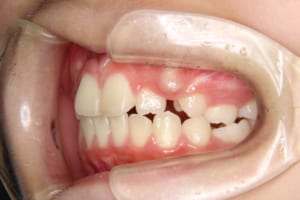

治療前

| 年齢・性別 | 11才 女性 |

| 主訴 | 八重歯の生え方が気になる |

| 治療内容 | 子どもの矯正治療(前期治療) マルチブラケット装置を使用した大人の矯正治療(後期治療/成人矯正治療)を行いました。 |

| 治療期間 | 子どもの矯正治療:2年1か月 大人の矯正治療:2年4か月 |

| その他/備考 | 上の犬歯が生えるためのスペースが全くない状態でした。放置すると重度の八重歯になることが想定されるケースです。 今回はあごの成長も利用しながら治療をするために、早めに後期治療(大人の矯正治療)に移行しました。 治療後レントゲン写真を見たところ、上顎前歯に若干の歯根吸収を認めました。 |